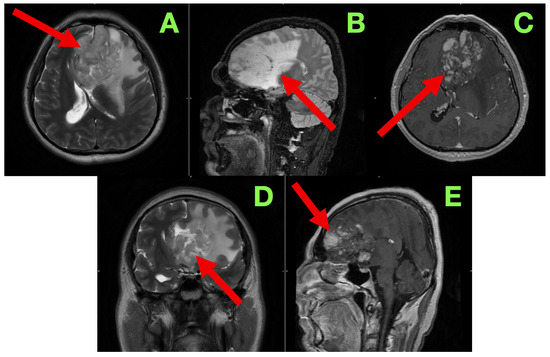

A non-contrast cranial CT scan was obtained within 4 h of the procedure to evaluate the resection cavity and rule out acute complications (Figure 2).

Figure 2. Immediate post-operative non-contrast CT scan. (A): Axial section showing a well-defined hypodense surgical cavity in the left frontobasal region (red arrow), corresponding to the zone of resection. No acute hemorrhage is present. A thin hyperdense rim along the cavity walls likely represents blood residue and oxidized cellulose (hemostatic material). (B): Coronal reconstruction demonstrating the vertical extent of the resection cavity (red arrow), which reaches the superior frontal gyrus and approaches—but does not breach—the genu of the corpus callosum. The midline remains centered, with no evidence of subfalcine or transtentorial herniation. (C): Lower axial slice illustrating the anterior margin of the resection cavity (red arrow). The basal ganglia and anterior limb of the internal capsule are preserved, and no new infarct or hematoma is detected. (D): Coronal view confirming decompression of the previously compressed left frontal horn (red arrow). No hydrocephalus or extra-axial collections are present. A subtle air–fluid level is visible within the cavity, consistent with expected early post-operative change.